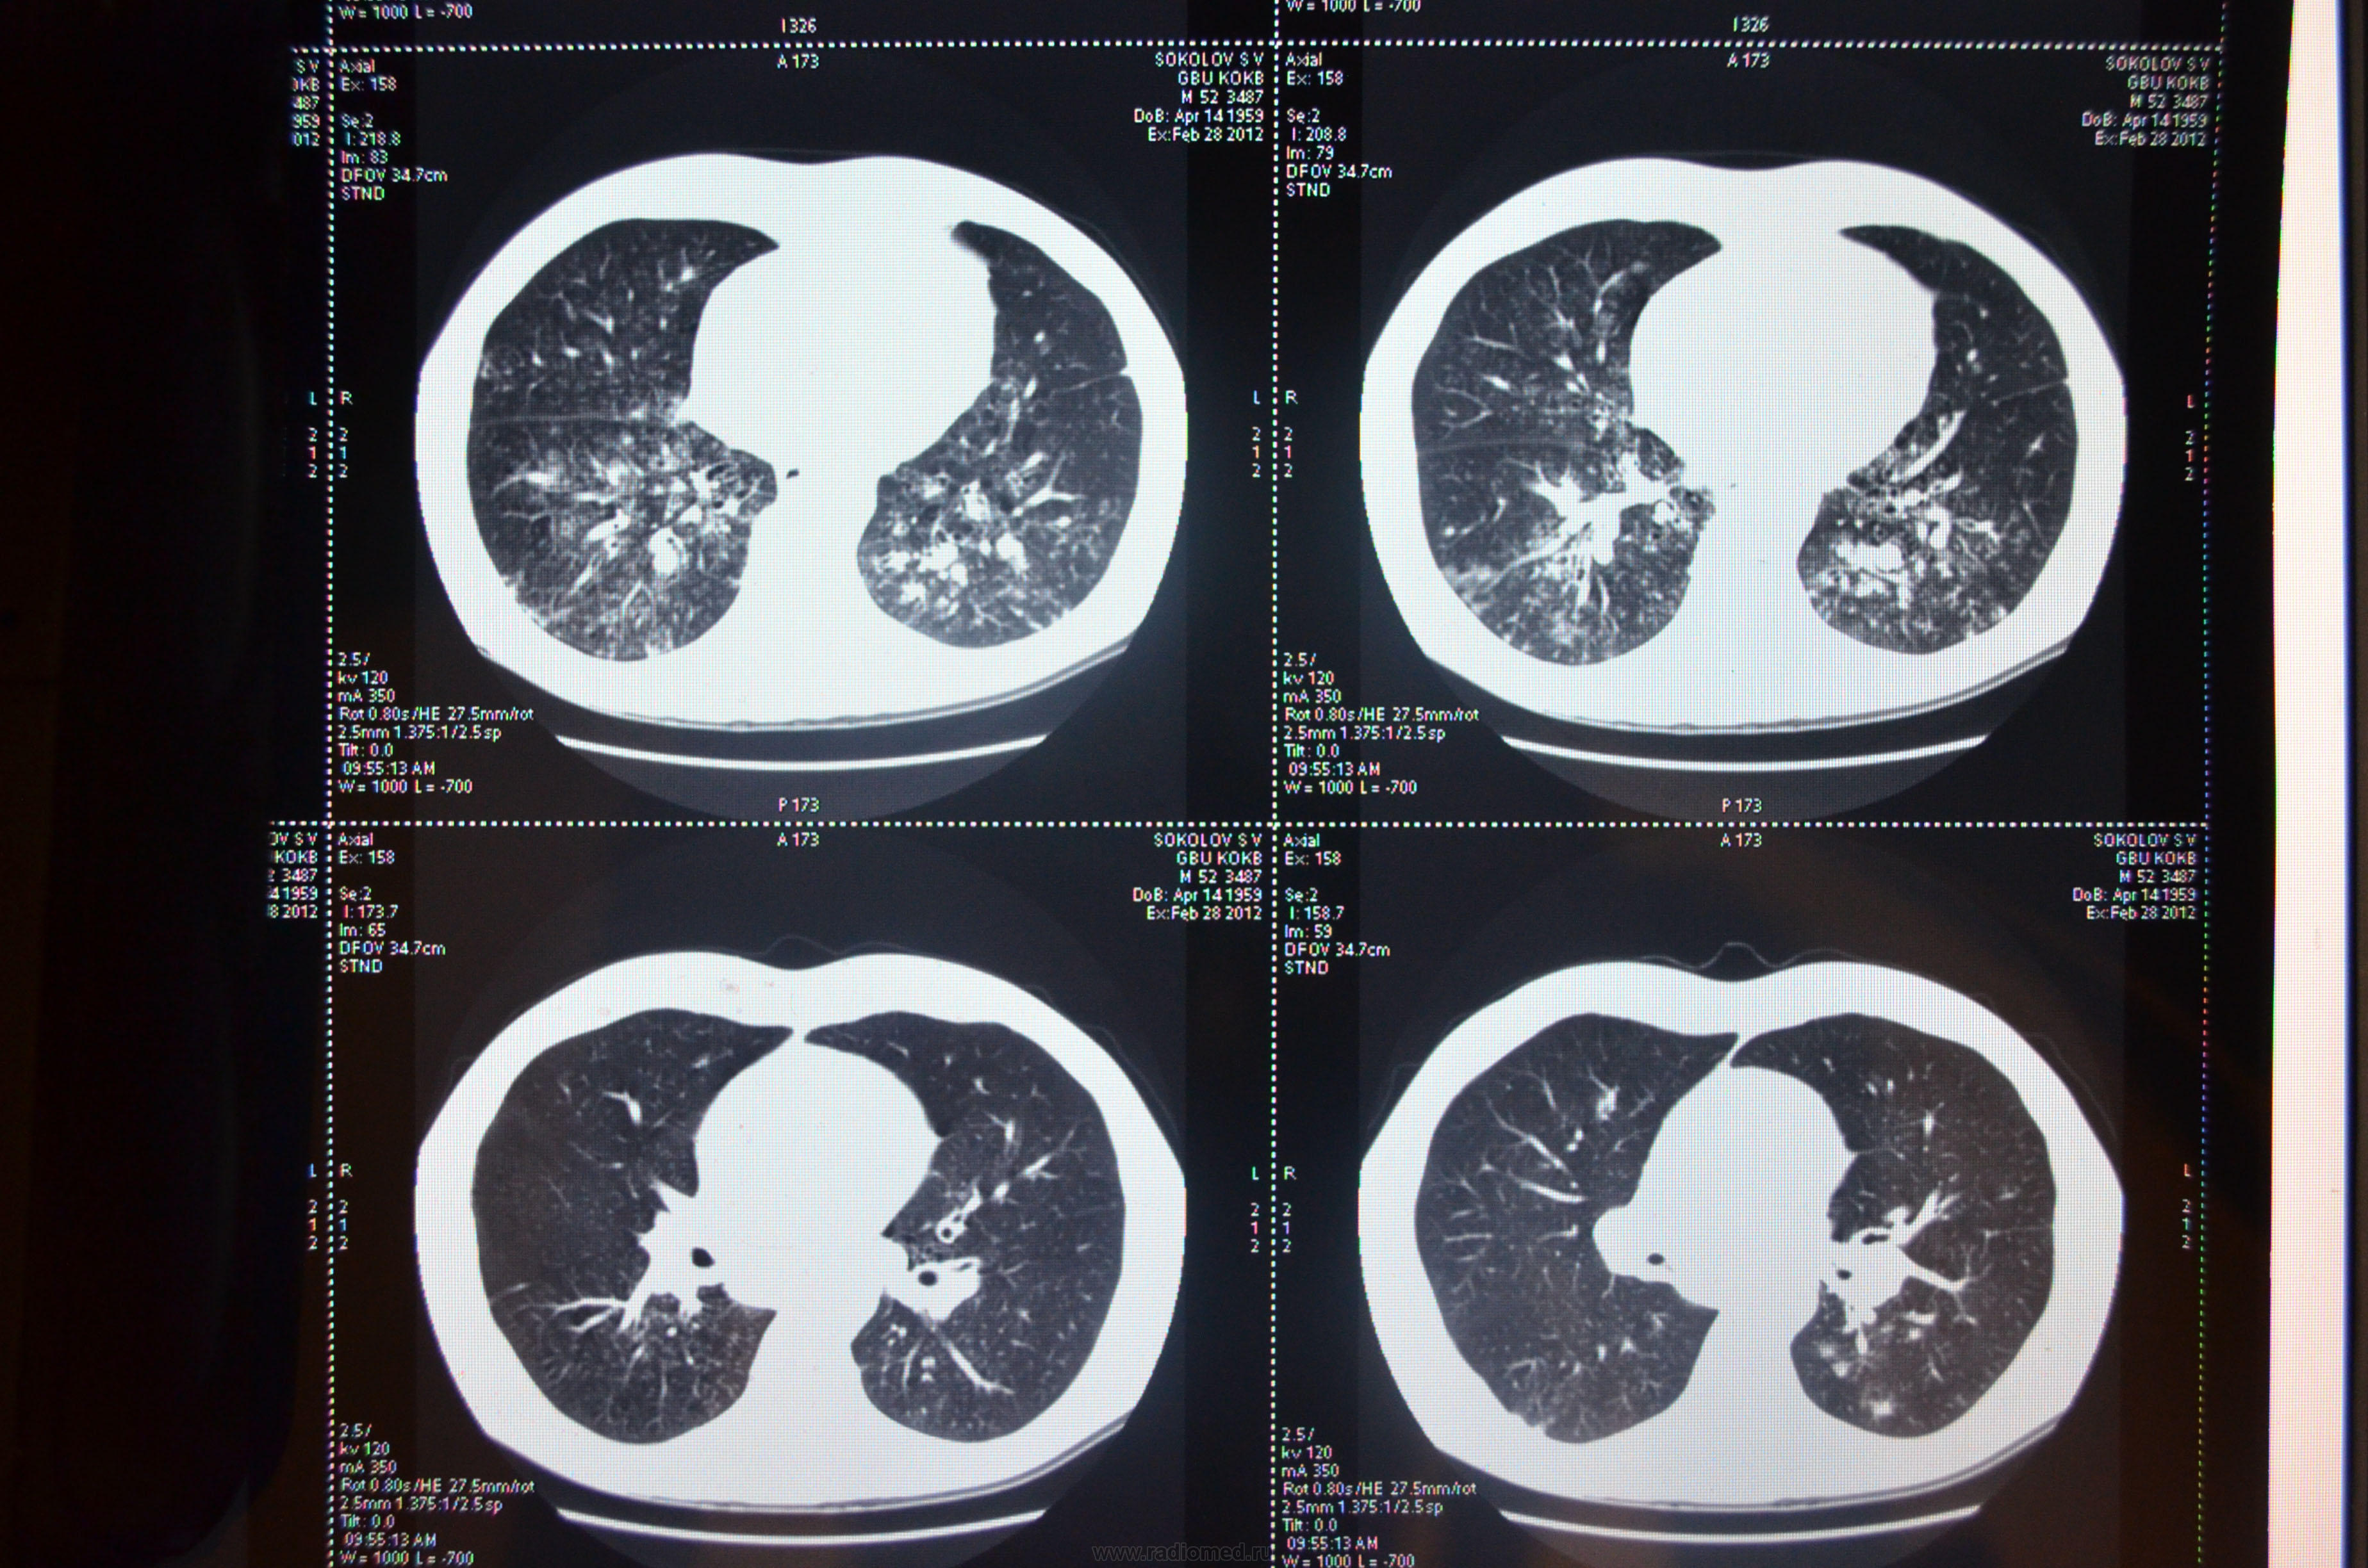

КТ ОГК (09.02.12): КТ-картина двусторонней пневмонии. Медиастинальная лимфоаденопатия.

КТ ОГК(28.02.12): Больше данных за двустороннюю пневмонию на фоне бронхоэктатической болезни.

Результаты анализов оценить и методы лечения рекомендовать может лечащий врач. По КТ (насколько можно рассмотреть) и анализам - вероятен кандидоз, грибковое поражение легких.

То что видим – переснято с монитора.

Может быть есть запись исследования на диске?

Либо метастатический процесс.